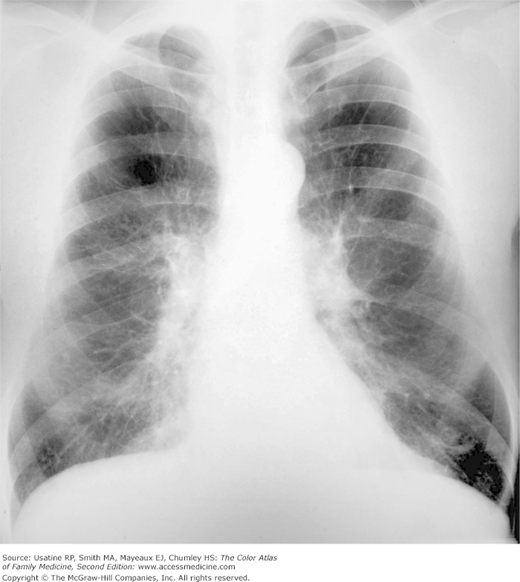

Clear Chest X Ray Copd . Interstitial lung disease, lung cancer with airway obstruction. The resulting image may reveal enlarged lungs, a. This exam can help support the diagnosis of copd by producing images of the lungs to evaluate symptoms of shortness of breath or chronic cough.

Interstitial lung disease, lung cancer with airway obstruction. This exam can help support the diagnosis of copd by producing images of the lungs to evaluate symptoms of shortness of breath or chronic cough. The resulting image may reveal enlarged lungs, a.